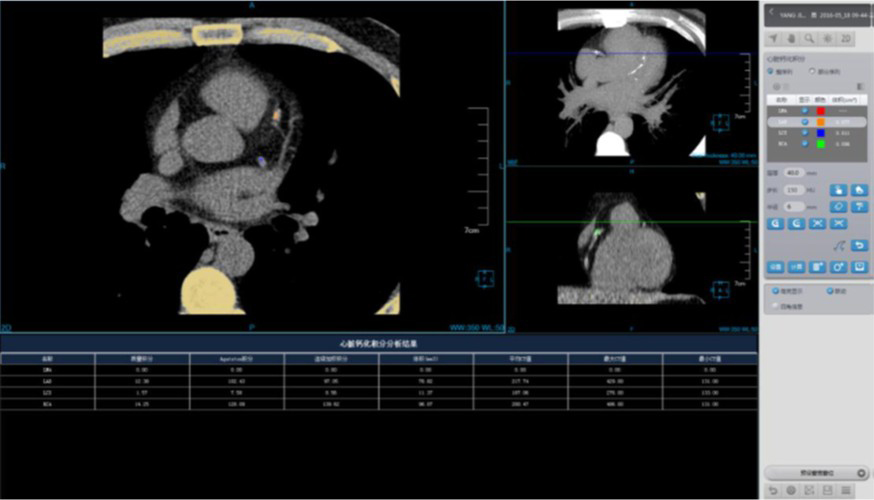

Coronary Calcium Scoring

Estimate the amount of calcium in the coronary arteries

• Agatston score

• Volume score

• ROI information calculation

Cardiac Function Analysis

Analyze a variety of heart functions

• Left ventricular volumes Ejection fraction

• Left ventricle wall motion and thickening

• 4D Rendering

One Station Cardiac Diagnosis Analysis